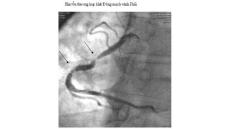

Tôi được biết hiện nay có phương pháp chụp động mạch vành qua đường ống thông để chẩn đoán chính xác bệnh động mạch vành, phương pháp này như thế nào? Khi nào cần...